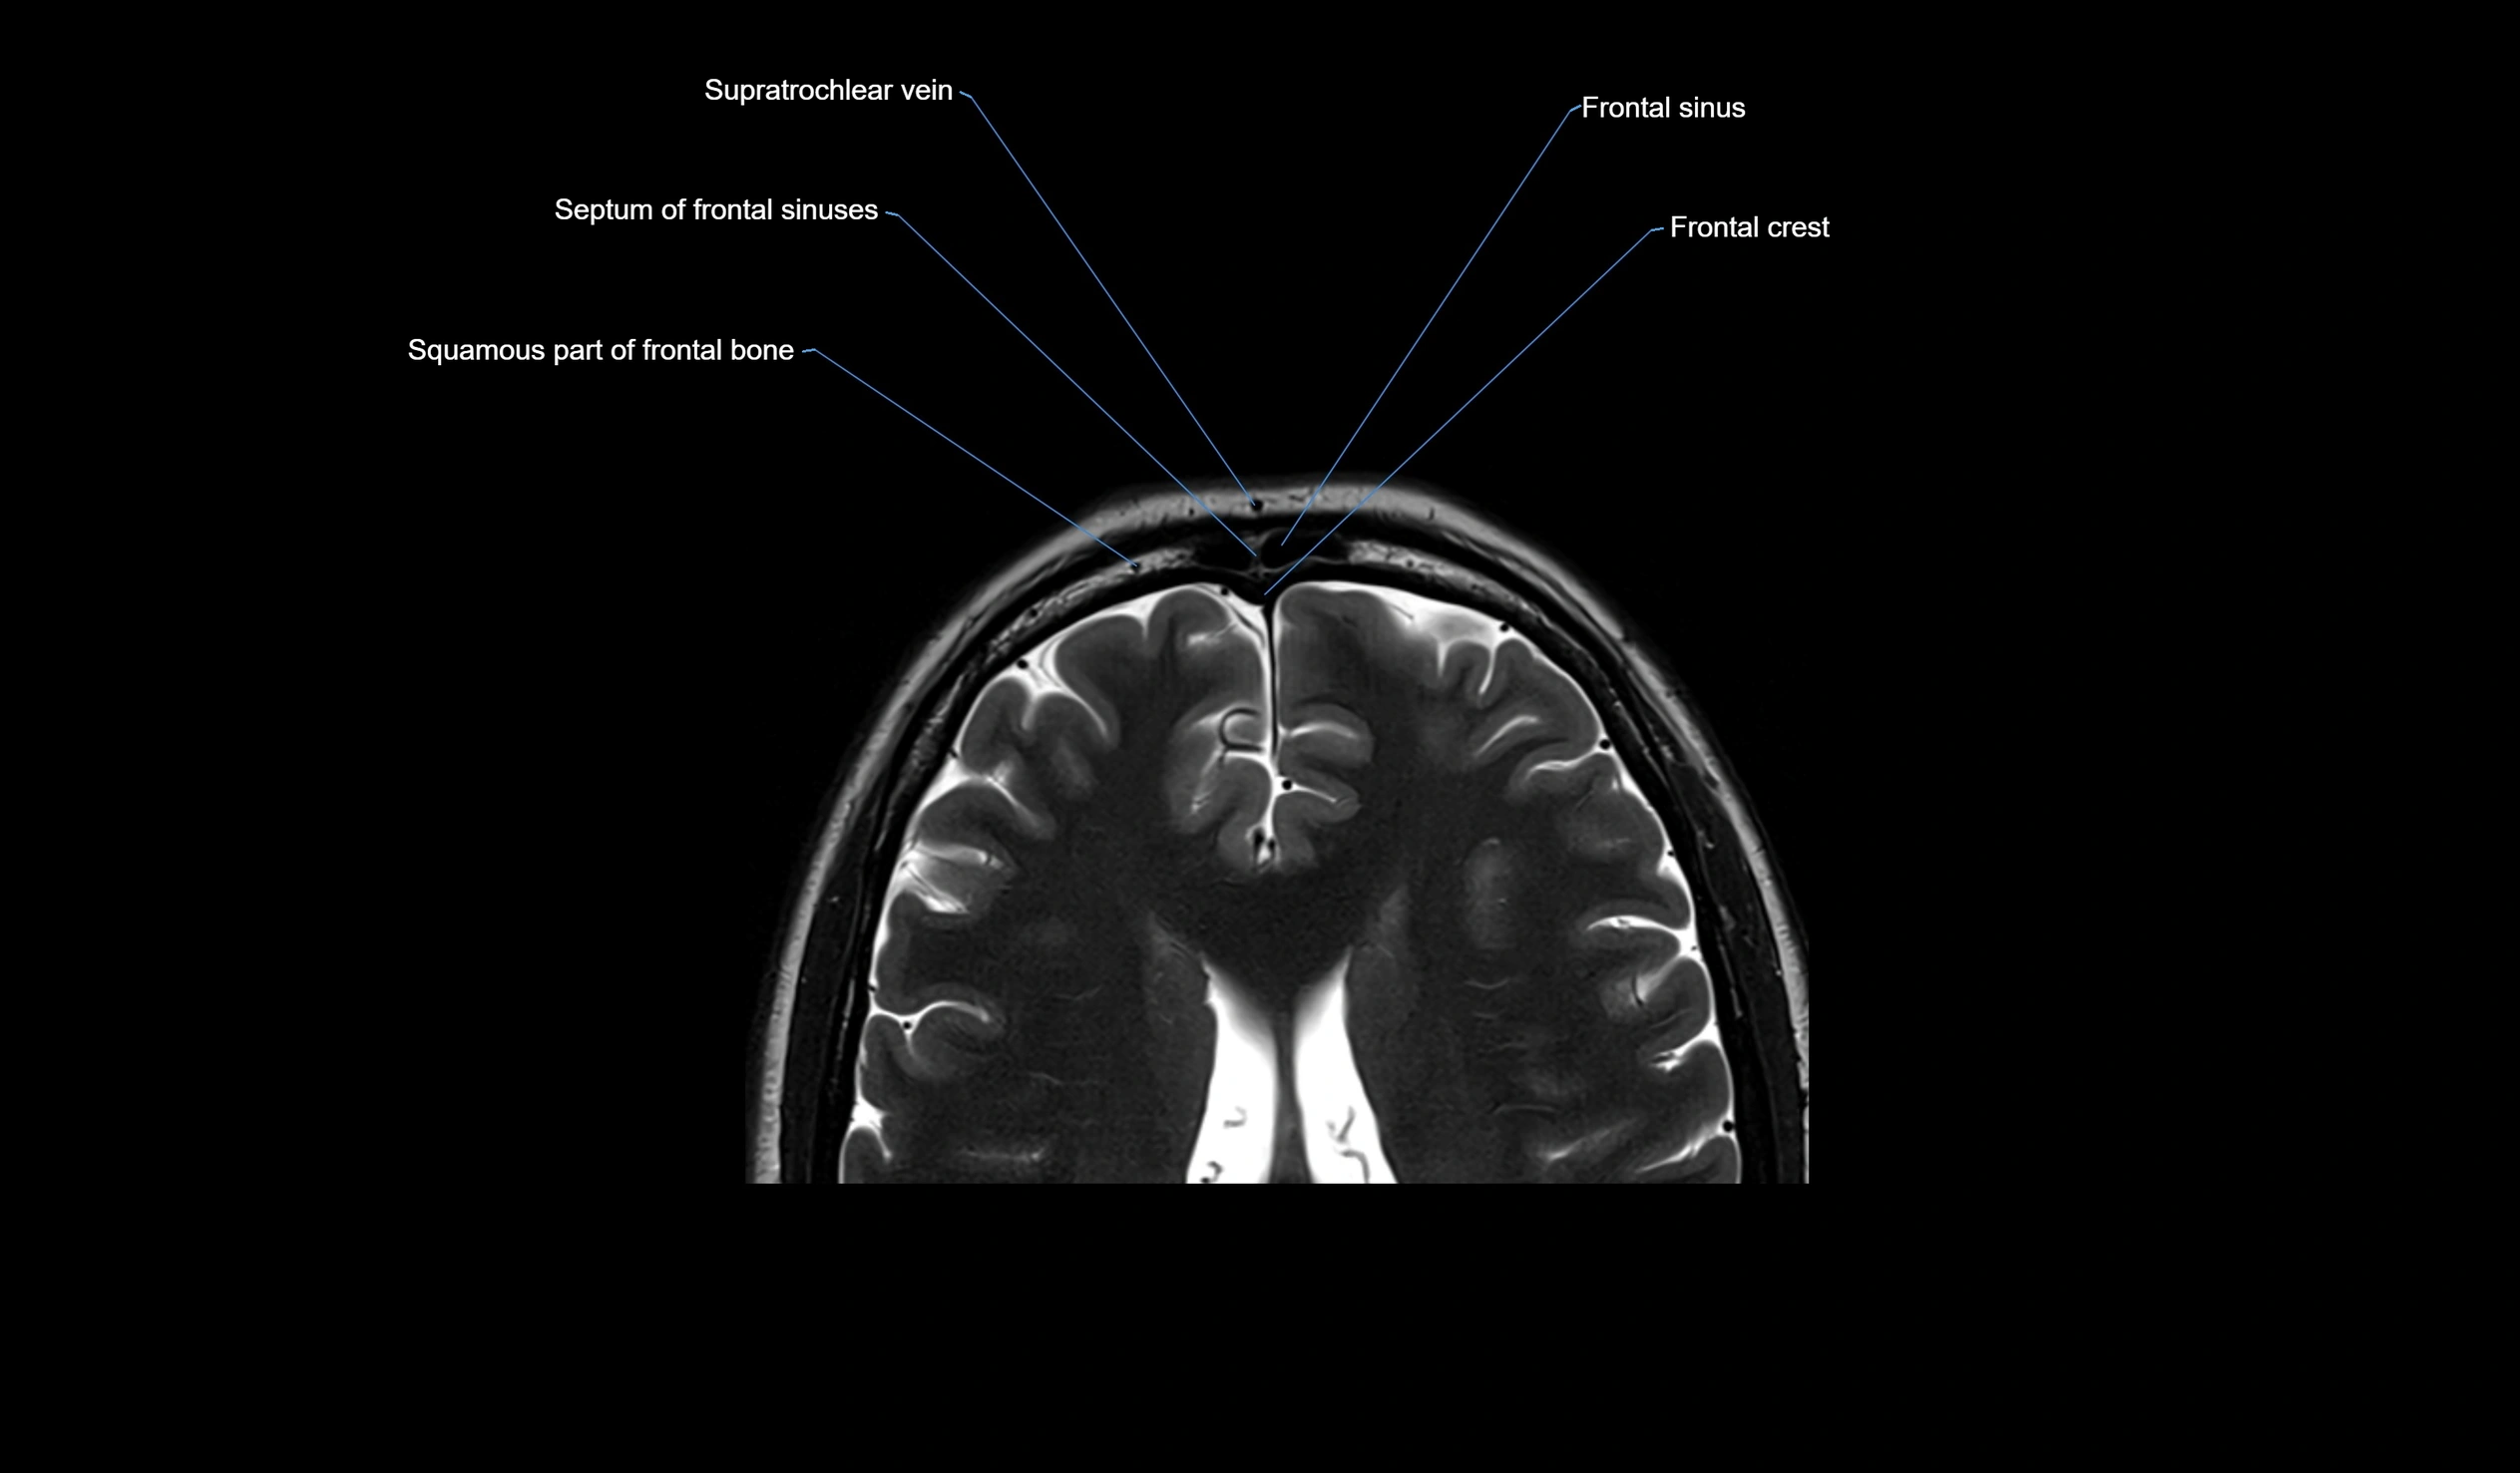

MRI images